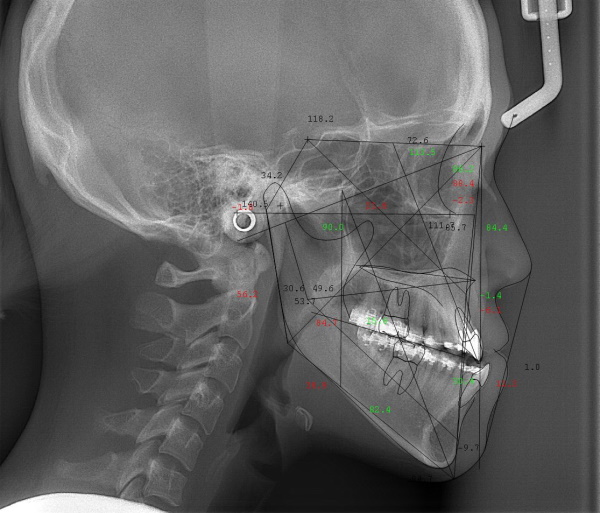

顎矯正手術(外科矯正)は、通常の矯正歯科治療だけでは改善が難しい、歯や骨格の問題が深刻な場合に採用される治療法です。通常の歯の矯正治療に加えて、顎の骨を手術によって移動させることで、噛み合わせを改善します。これにより、歯の並びだけでなく、上下顎の骨格の位置やバランスに起因する問題も解決することが可能です。骨格的な偏位や大きさの問題、バランスの崩れなどが原因で、通常の歯の矯正治療だけでは解決しづらい場合に、外科矯正が選択されます。

川崎市からご来院の20代女性で、受け口(反対咬合)と交叉咬合(すれ違い)の症状がありました。

治療法は裏側矯正(舌側矯正)で、治療期間は2年です。

非抜歯で矯正治療を行い、キレイな歯並びになりました。